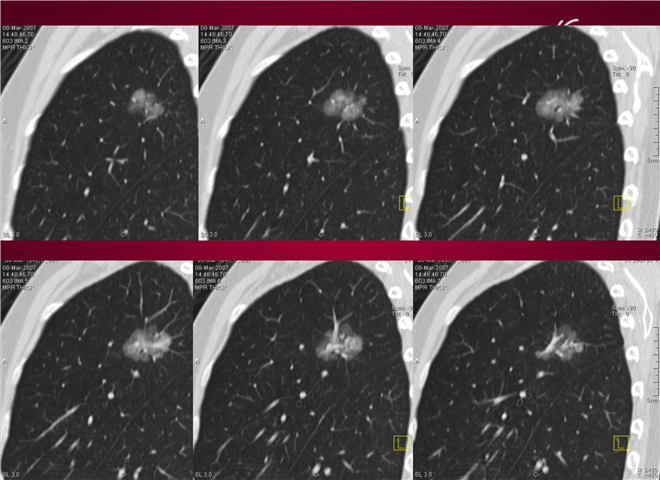

23_CT读片基础